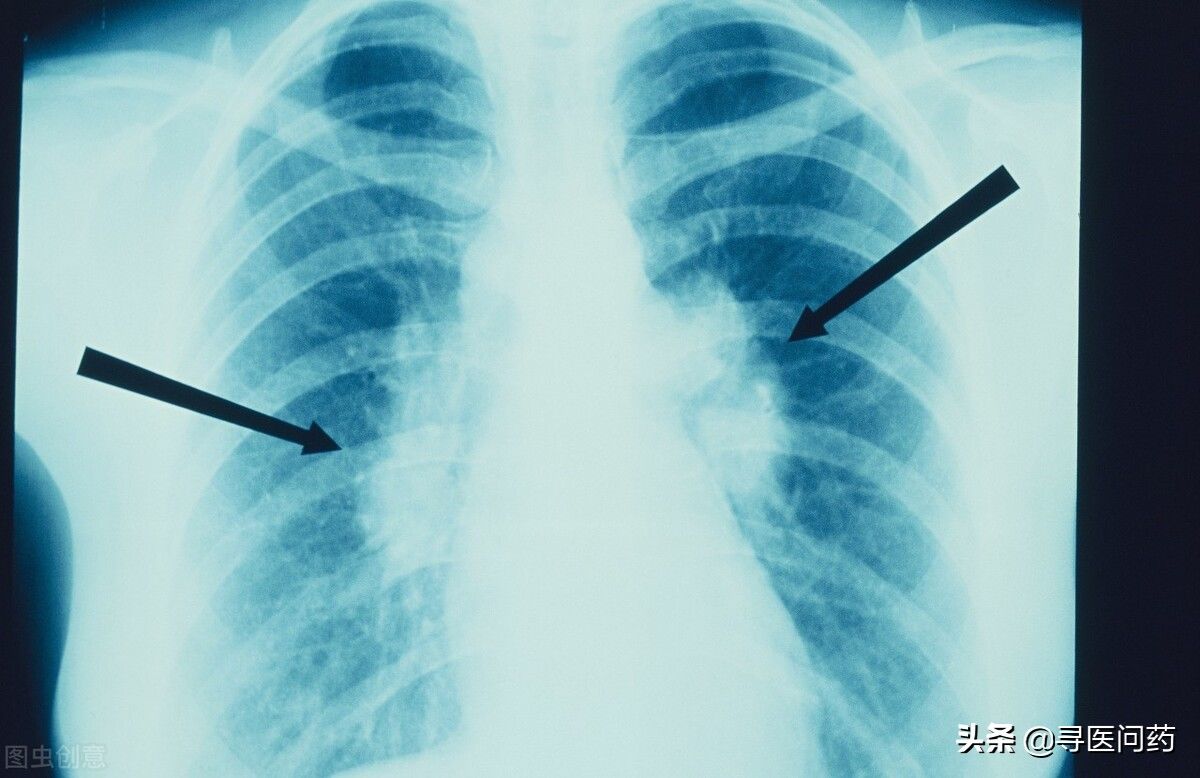

肺结节是肺内占位性病变。根据其直径大小来定义,肺内直径≤3cm的类圆形或不规则形病灶,可单发或者多发,我们称之为肺结节。肺结节直径在0.5cm-1cm属于肺小结节,直径>3cm则称为肿块。

直径d>0.8cm的肺结节,需要根据具体情况,进行非手术活检、手术切除、放化疗、随访等处理。